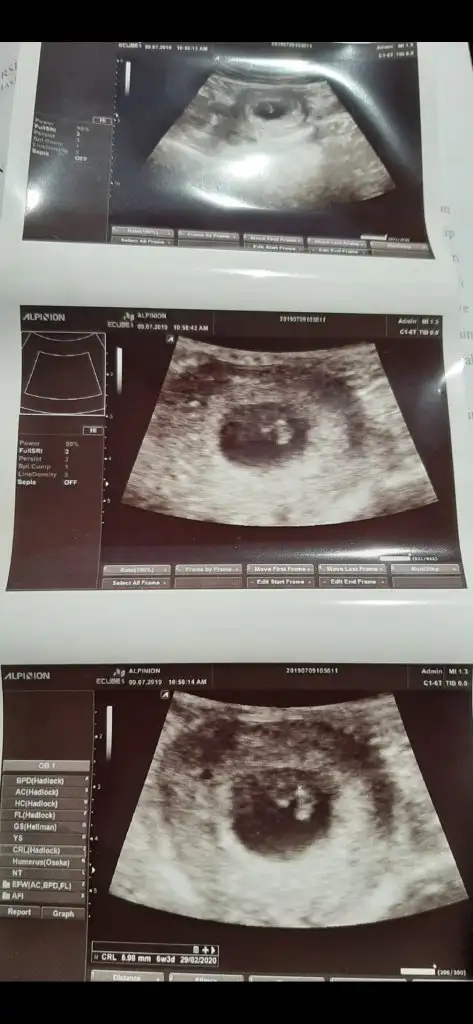

Sag taraf uste buna göre kız ama siz yinede 11 yada 12 hafta usg paylaşınMerhabalar:) 6 haftalik karından ultrason görüntüsü. Tahminlerinizi paylaşırsanız sevinirim :)

Başka bir postta paylaşmıştım erkek tahmin ettiniz bakalım hangi teori tutacak :)))Sola yakın vajinal usg buna göre kız ,ama siz 11 yada 12 hafta nub için usg paylaşın